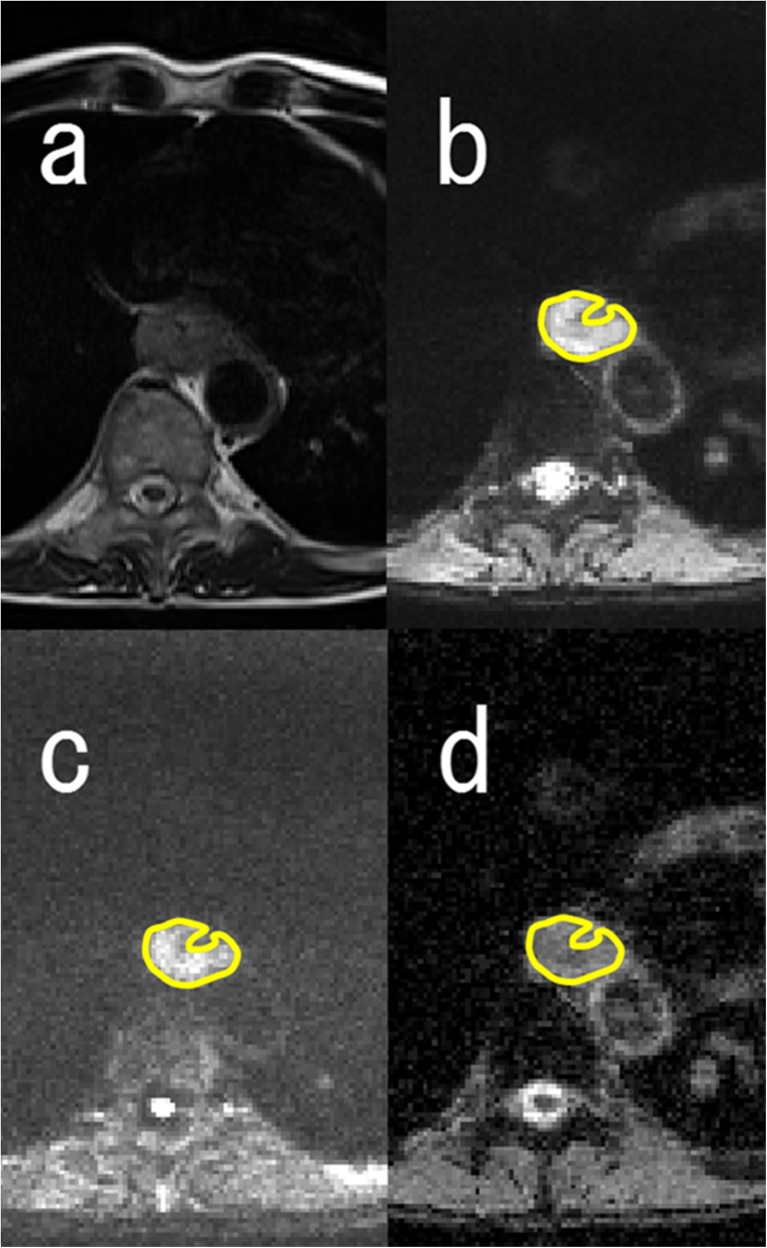

MR image interpretation

Two board-certified radiologists with 12 years’ experience of body imaging and 4 years’ experience of radiation oncology evaluated the MR images by consensus reading. They were blinded to subjects’ clinical information and CT images. MR imaging data for ADC maps were transferred to a personal computer and processed with Image J software (http://rsb.info.nih.gov/ij/). All region of interest (ROI) placements on DWI with b = 50 s/mm2 were decided by the two readers referring to the outline of the tumour that showed intermediate to high intensity with oesophageal wall thickening on T2-weighted images. Each ROI was placed to cover the entire primary lesion without the lumen in multiple slices (in craniocaudal direction also) and was transferred to the corresponding ADC map (Fig. 1).

Fig. 1.

Axial MR images. a T2-weighted image, b diffusion-weighted image (DWI) with b = 50 s/mm2, c DWI with b = 800 s/mm2 and d apparent diffusion coefficient (ADC) map of a 62-year-old man with oesophageal squamous cell carcinoma. Region of interest (ROI) placement on DWI with b = 50 s/mm2 (b) was performed by referring to the outline of the tumour that showed intermediate to high intensity with oesophageal wall thickening on T2-weighted images (a). Each ROI was placed to cover the entire primary lesion without the lumen and was transferred to the corresponding ADC map (d)